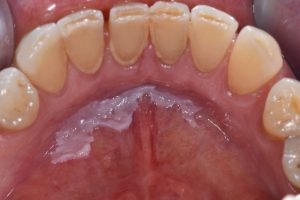

Mancha branca na mucosa bucal não removível à raspagem. Pode ser um sinal de alterações celulares que, se não tratadas, podem se transformar em câncer.